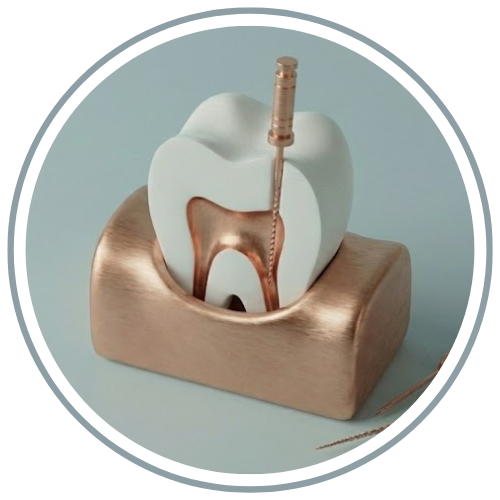

دندان عقل آخرین دندانی است که در دهان رویش مییابد و اغلب به دلیل کمبود فضا، به صورت نهفته یا نیمه نهفته باقی میماند. این مسئله میتواند باعث درد، عفونت، و آسیب به دندانهای مجاور شود. در کلینیک دندانپزشکی مهر، ما با بهرهگیری از تجهیزات مدرن و رادیوگرافی دیجیتال، موقعیت دقیق ریشه دندان را بررسی کرده و جراحی را با کمترین آسیب به بافت لثه انجام میدهیم.

فرآیند و مراحل جراحی دندان عقل در مرکز مهر

در ویدیوهای زیر، بخشی از فرآیند دقیق و تکنیکی جراحی دندان عقل توسط تیم تخصصی کلینیک مهر را مشاهده میکنید. این تصاویر نشاندهنده دقت در مراحل کار و استفاده از روشهای مدرن برای انجام ایمن جراحی است:

توجه: همانطور که در مراحل ویدیو مشخص است، جراحیها با نهایت دقت و با تکیه بر دانش تخصصی و تجهیزات پیشرفته در محیطی کاملاً کنترل شده در کلینیک مهر انجام میپذیرد.